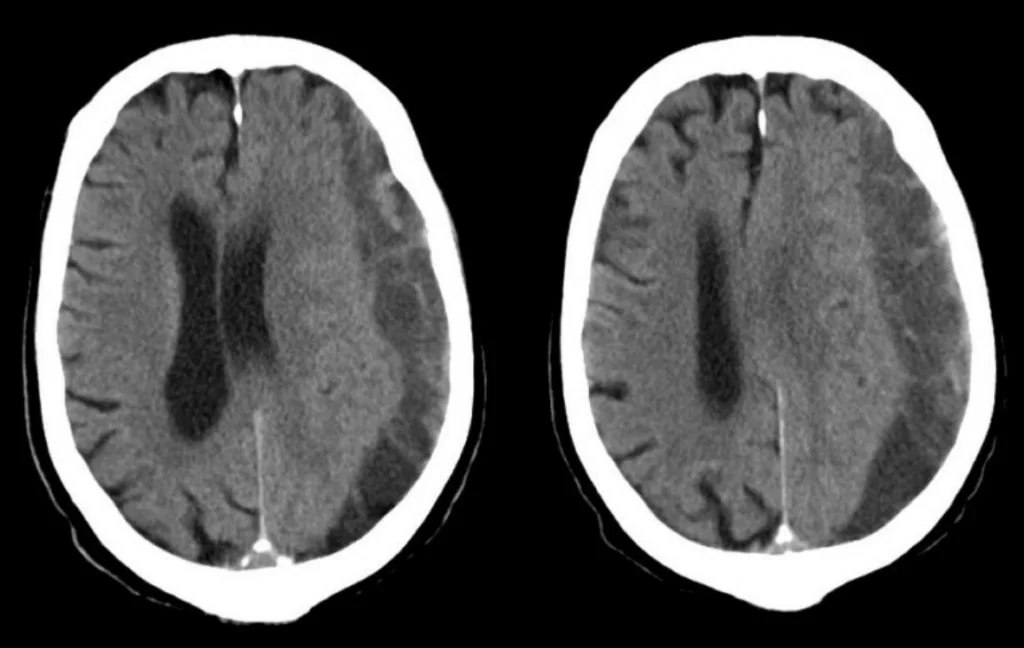

Οι ασθενείς με σημαντική εγκεφαλική ατροφία (Εικόνα 3) διατρέχουν υψηλότερο κίνδυνο για υποσκληρίδιο αιμάτωμα. Αυτή η κατηγορία περιλαμβάνει τους ηλικιωμένους, εκείνους με ιστορικό κατάχρησης αλκοόλ και αυτούς με προηγούμενη τραυματική εγκεφαλική βλάβη. Σε αυτούς τους ασθενείς ακόμα και ασήμαντο τραύμα στο κεφάλι μπορεί να προκαλέσει υποσκληρίδιο αιμάτωμα. Έτσι, το υποσκληρίδιο αιμάτωμα παρατηρείται συχνότερα σε ηλικιωμένους ασθενείς παρά σε νεότερους.

Πολύ σημαντικό ρόλο παίζει η αξονική τομογραφία εγκεφάλου (Εικόνα 4). Σε έναν ασθενή με κρανιοεγκεφαλική κάκωση, η αξονική τομογραφία θα δείξει αν υπάρχει υποσκληρίδιο αιμάτωμα ή και κάποια άλλη εγκεφαλική βλάβη, όπως για παράδειγμα εγκεφαλική θλάση, επισκληρίδια ή υπαραχνοειδής αιμορραγία, κάταγμα κ.ο.κ.

Αλλά ακόμα και αν δεν έχει προηγηθεί κάκωση κεφαλής, η αξονική τομογραφία θα βοηθήσει να ελεγξουμε αν υπάρχει χρόνιο υποσκληρίδιο αιμάτωμα ή κάτι άλλο, όπως πχ. κάποιο ισχαιμικό εγκεφαλικό ή εγκεφαλική αιμορραγία. Η μαγνητική τομογραφία δε χρησιμοποιείται τόσο συχνά, έχει όμως πολύ μεγάλη ακρίβεια στο να αναδεικνύει ένα υποσκληρίδιο αιμάτωμα και μπορεί επίσης να αναδείξει και άλλες συνοδές εγκεφαλικές βλάβες.